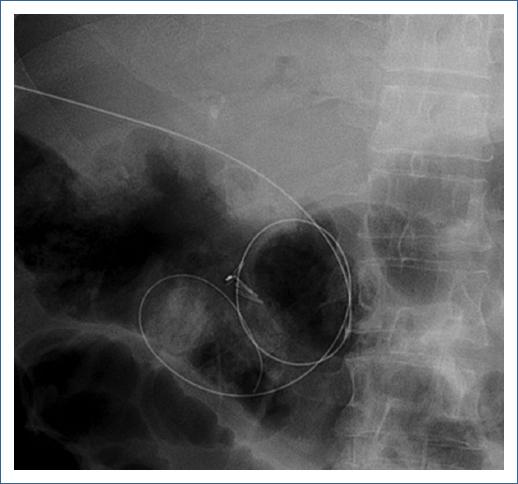

First, a colonoscope (190 Olympus Medical Systems, Tokyo Japan) was passed up to the choledochojejunostomy, which was found kinked and angulated. Therefore, the colonoscope was withdrawn and an enteroscope (EVIS EXERA II [SIF-Q180], Olympus Medical Systems, Tokyo Japan) was passed until the kinked choledochojejunostomy. Second, a hydrophilic Guidewire (0.035 mm Jagwire Revolution High Performance Guidewire, Boston Scientific Corp) was introduced percutaneously into the biliary tree under transabdominal ultrasound assistance to access the afferent limb (Fig. 1), and the guidewire was recovered with the enteroscope (Fig. 2). Third, the enteroscope holding the guidewire was withdrawn and interchanged into a stent-loaded colonoscope. Finally, the colonoscope holding the guidewire was introduced and an enteral uncovered self-expandable metal WallFlex Duodenal Stent, Boston Scientific Corp (22 mm × 60 mm) was successfully deployed at the site of the obstruction (Fig. 3). The schematic representation of the technique is described in figure 4. The patients evolution was satisfactory and was discharged 48 h after the procedure.

Figura 4 Schematic representation of the rendezvous technique and endoscopically stent placement. (1) A hydrophilic guidewire is inserted percutaneously through the kinked choledocojejunostomy (asterik) to bypass the afferent limb (red shadow). (2) The enteroscope is advanced to retrieve the guidewire (3) and a metal stent is deployed with a colonoscope (4) with resolution of the afferent limb syndrome.